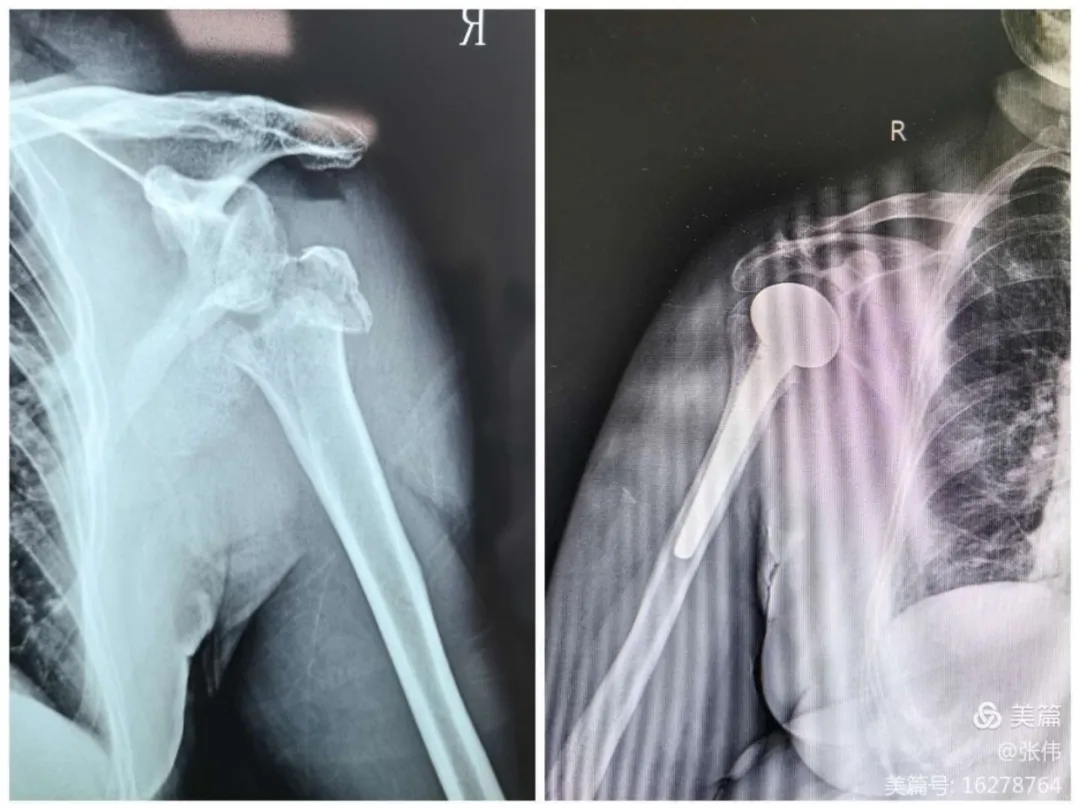

我院骨科近期成功为两名肱骨近端粉碎性骨折伴脱位的79岁高龄患者实施半肩关节置换术。

肱骨近端骨折伴脱位的高龄患者在骨关节不能复位情况下,通过传统手术采取接骨板内固定术,会因为骨质疏松、粉碎性骨折导致内固定失效、肱骨头坏死等较高风险。我院开展半肩关节置换术,降低了老年患者的手术风险,减轻了老年患者的术后疼痛,提高了老年患者的生活质量。